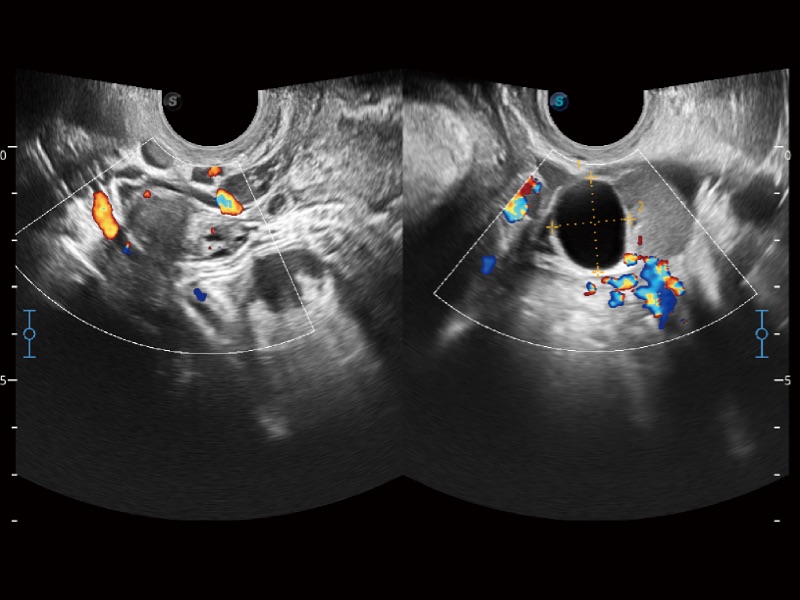

• SR Flow 高分辨率血流成像技术

高分辨率血流成像技术提高了对低速血流信号的检测能力。在提高空间分辨率的同时,也克服了血流外溢现象,为用户提供更加真实的血流动力学信息。